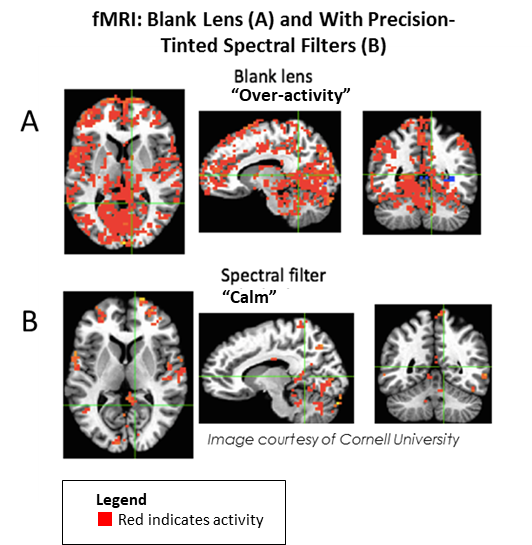

Individuals with Irlen Syndrome will often complain of light sensitivity associated with sunlight, bright lighting, fluorescent lights, headlight and glare. They may also have reading problems, as reading becomes inefficient and they may need to re-read for comprehension or build breaks into reading. High contrast (black print on white paper) and visually-intensive activities, create high levels of stress for the brain that trigger physical symptoms which may include headaches and migraines. Brain imaging, both SPECT scans and fMRI, of individuals with this condition shows over-activity, complex brain patterns and non-normalised functioning. This results in a variety of issues, including difficulties reading because of a lack of print stability, issues with glare or discomfort from the white background on the printed page, problems with depth perception and physical symptoms, such as headaches, nausea, dizziness, brain fog, anxiety, strain and fatigue.

Ongoing research by Drs. Adam Anderson and Eve De Rosa at Cornell University’s fMRI facility in the United States shows over-active brain function when Irlen Syndrome sufferers wear a blank lens that normalises when the proper precision-tinted colored filters are worn.